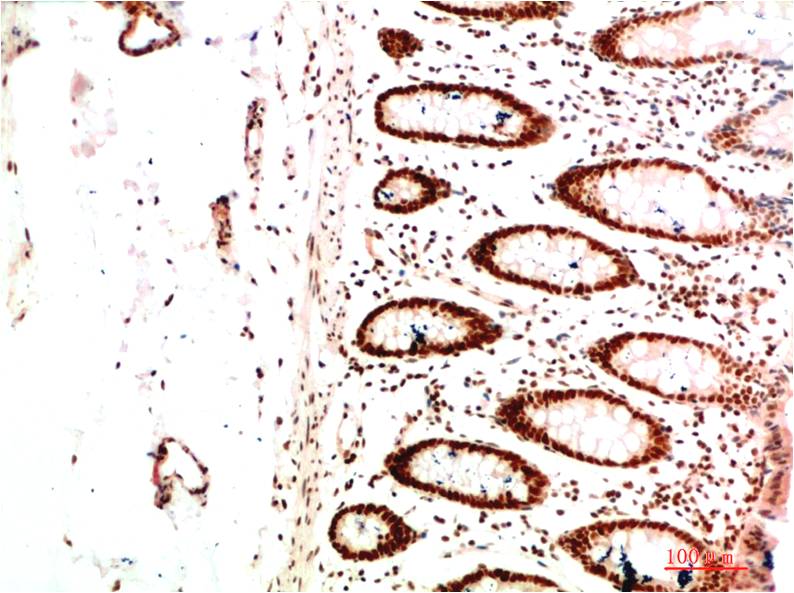

Immunohistochemical analysis of paraffin-embedded Human tonsils using HP1 alpha antibody.High-pressure and temperature Sodium Citrate pH 6.0 was used for antigen retrieval. |